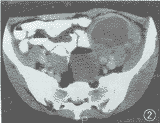

图2 左中下腹大网膜上一直径约9 cm囊状强化肿块,壁光滑,囊内为均匀低密度区,无强化(CT值18 HU)。病灶周围有多个结节状小病灶,呈均匀强化